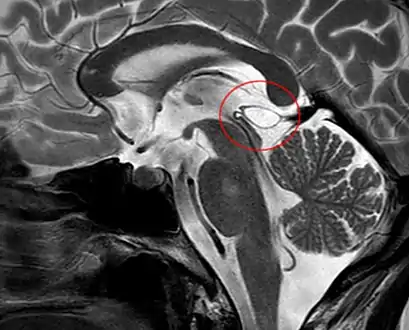

| Pineal gland cyst | |

Another case: sagittal